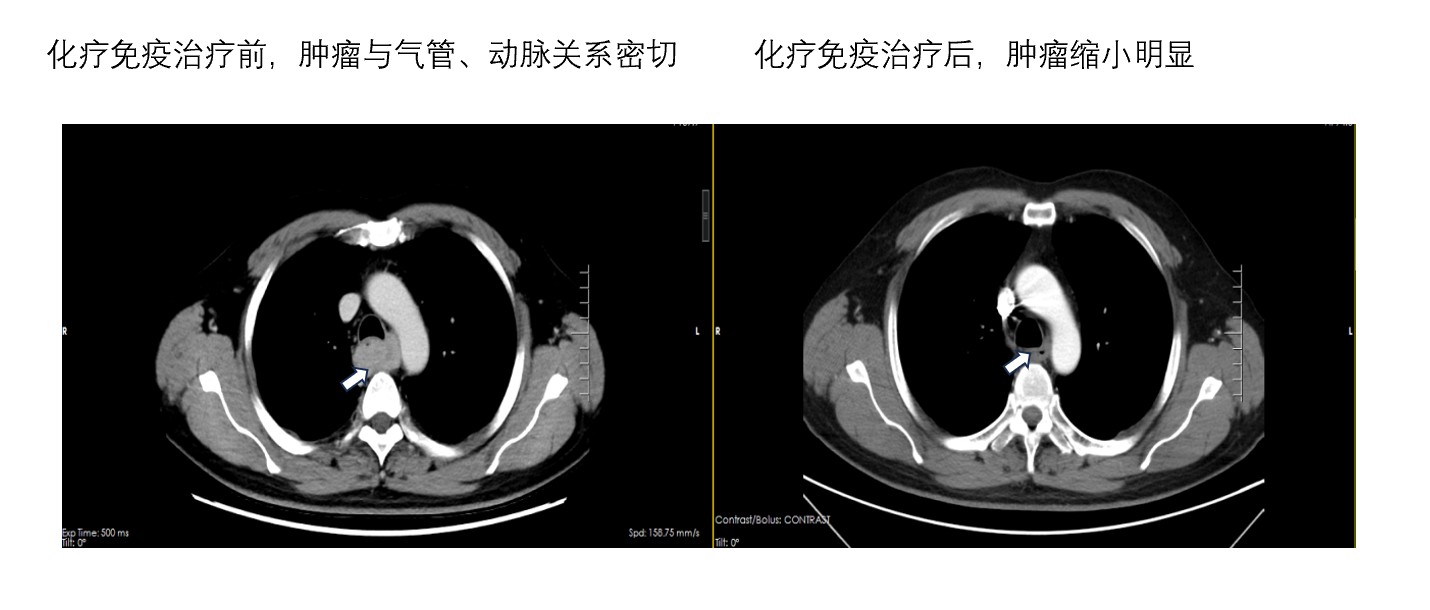

随后,该患者进行了两次化疗联合免疫治疗,经过顺利,没有出现明显的不良反应。复查CT结果正如我们所预计的那样,肿瘤明显缩小了,与周围的血管、支气管间隙变得清晰,此时正是手术介入的时机。于是,我们立即在全麻下行“胸腹腔镜微创三切口食管癌根治术”,由于肿瘤退缩效果不错,此时的手术对我们来说犹如探囊取物,术中切除和术后康复均非常顺利。术后病理:(食道)检材见极少许变性癌组织残存,残存癌组织位于黏膜层内;切缘未见癌;淋巴结31枚均未见转移。此时,肿瘤疗效达到明显缓解,已有研究证明,这类患者治疗效果最好。随后,该患者又继续化疗+免疫治疗2周期,免疫单药维持治疗一年。随访至今三年没有肿瘤复发,患者日常生活基本正常。